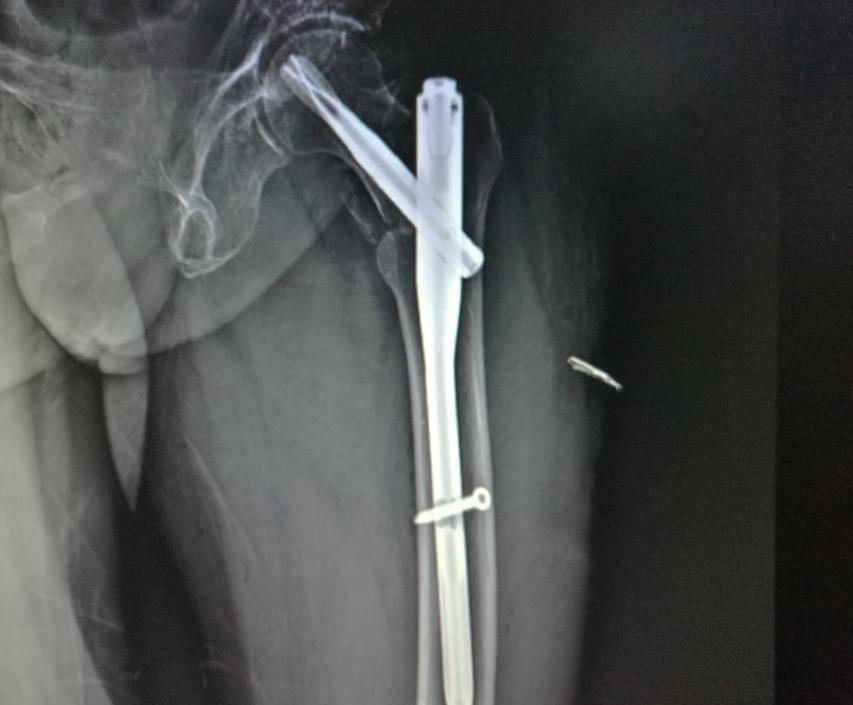

第四名:股骨骨折

被排名第四位的是股骨骨折。

提到骨折,任何一根骨头骨折都让人难以招架,更何况是你体内最粗壮、最坚固的骨头——股骨骨折。

人的股骨是下肢主要负重骨之一。

再加上沿着腿部延伸的所有大动脉,如果不幸股骨骨折,这骨折会占人体全身骨折的4%-6%,那真的要痛不欲生。

股骨骨折一般是因为,某种严重事故(例如运动损伤或车祸)引起的,当该区域骨折时,碰到一点儿都会立即让人们尖叫。

就不用说在受伤的腿上,施加任何重量,更不用说是在行走了。

老年人也是股骨骨折的高发人群。

这主要是由于老年人的骨矿物质密度降低,从而导致骨折易感性增加。并且髋周肌群退化,反应能力下降,无法减轻或抵消外来压力而造成的。

大家都知道,骨折那恢复起来是很慢的。

俗话说,伤筋动骨100天。更何况是股骨骨折,它的恢复过程也是相当艰难的。

首先得将骨头放回正确的位置,医生会通过手术放置一些“硬件”支撑。

然后,当身体再生新的骨头生长出来和原来的骨头,发生冲突产生炎症时,还须要用物理治疗,来加强骨的强度以及骨头周围的肌肉。

想一想就浑身发抖,难以想象股骨骨折,得给人们的生活带来多少不便和疼痛。